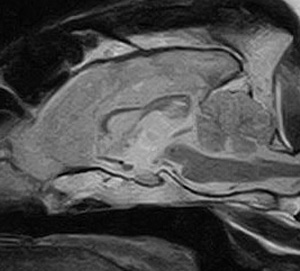

5~6歳以上の去勢手術をしていないオス犬に多い病気ですが、メス犬や去勢した犬に起こることもあります。お尻の筋肉が萎縮した結果、筋肉の隙間から直腸や膀胱が皮膚の下にとびでてしまいます。これにより便が出にくくなったり膀胱炎になったりします。手術をすることで機能回復および今後の致死的な状況を回避することができます。当院では去勢手術→結腸固定→前立腺固定→骨盤隔膜構成筋の縫縮→内閉鎖筋フラップ→浅臀筋フラップの順で通常腹側・臀部左右両側同時に行います。また老化以外に、筋肉が萎縮する原因があったり、腹圧がかかる原因があったりする場合も多いので、再発防止のためそれらの診断・治療も重要です。今回のワンちゃんも無事手術も終わり元気に退院しました。よかったね。